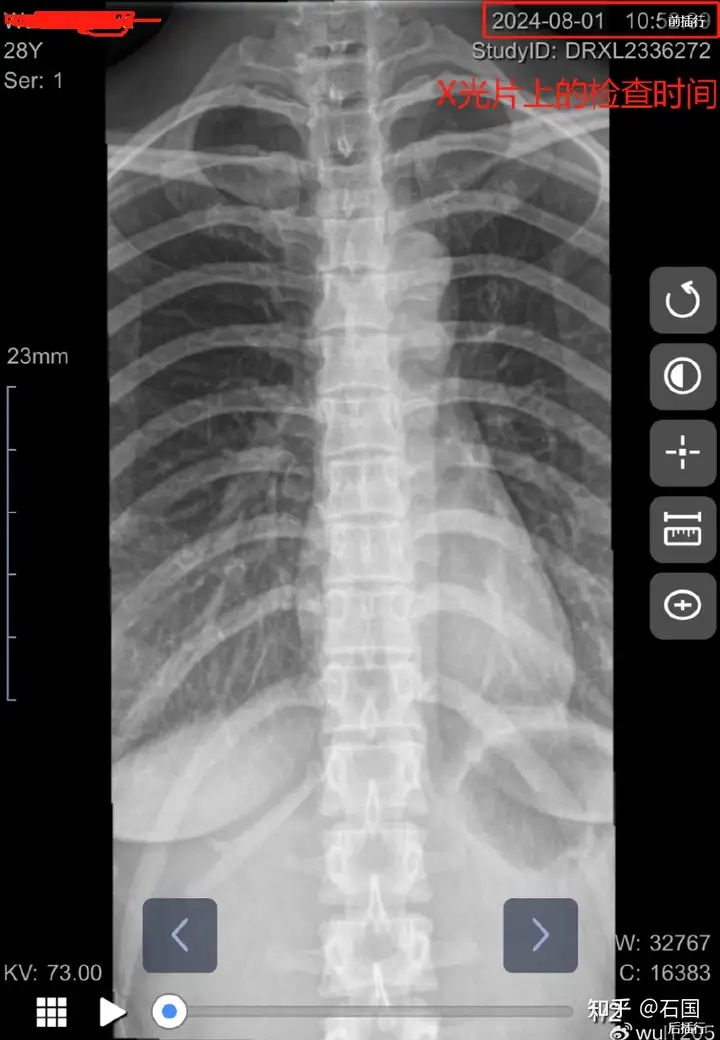

8 月 1 号,再次去该医院康复医学科就诊,告诉了赫*宇医生具 体情况,赫*宇医生给我做了 x 光片、心电图检查。 这种情况去任何一家医院,都会首选给我做 CT、核磁。 这里科 普一下,x 光片只能看骨头的情况,软组织和神经在 x 光片下不显影, CT 和核磁既能观察到脊柱骨头,又能看到神经软组织的情况。

但是,赫*宇医生为掩盖真相,隐瞒我神经软组织损伤的证据, 给我做的是 x 光片,既然都要考虑有没有骨折了,神经和软组织不用 考虑了吗?

而这是 X 光片上的时间

当时康复师站在我右边操作,可以看到,被压的那段脊椎整体 明显往右歪了 胸椎错位 凹陷,让我长达大半年时间都处在痛苦中